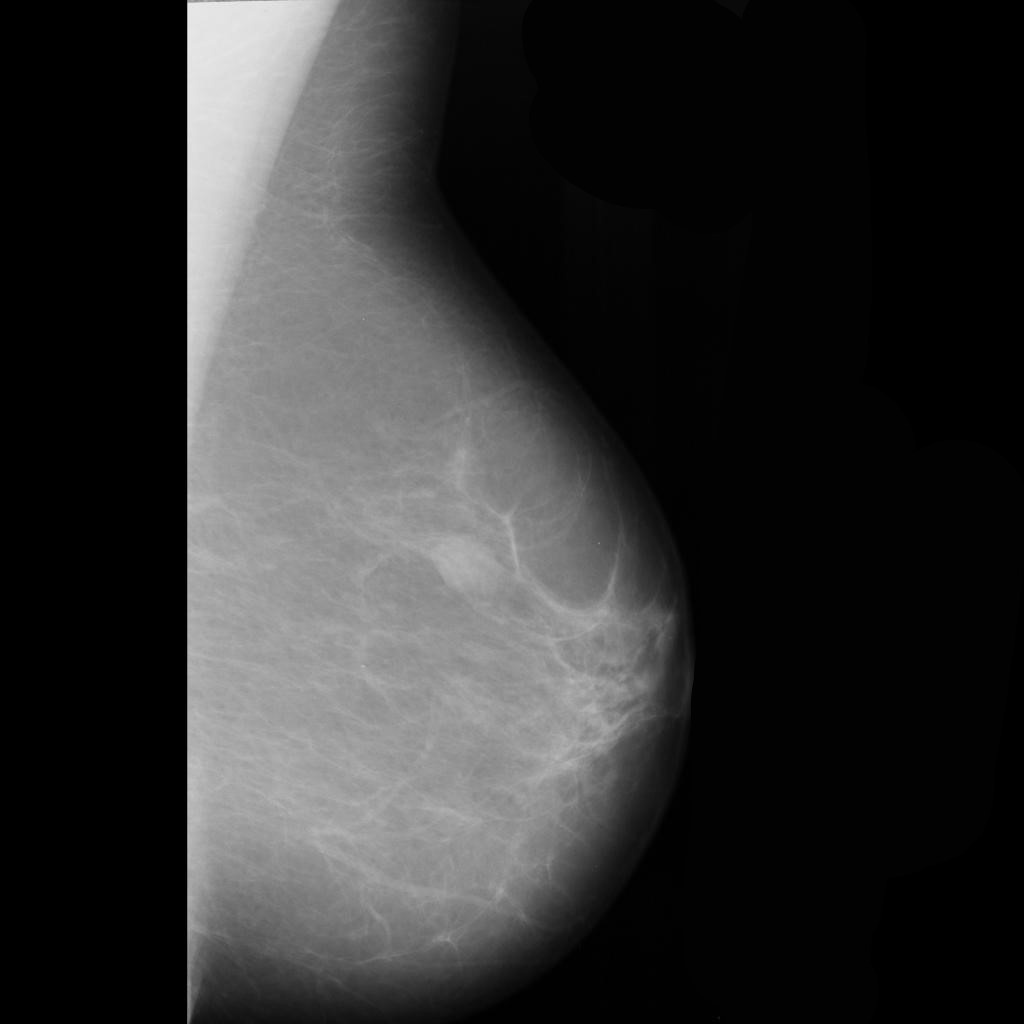

benign